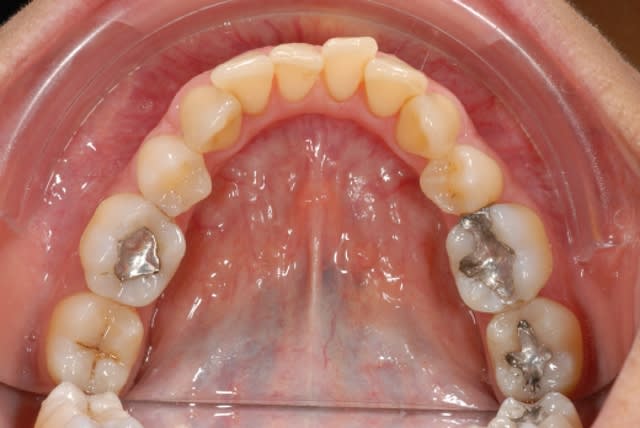

ma bouche à moi même :-)

et j'en suis là, parce que un jour un de vous m'a ratée.. eh oui, encore et toujours une récidive d'un traitement mal fini...

j'ai 4 PM en moins + 4 M3 en moins...bouhouhou

t'as pas vu le haut....la cata ;-)...t'as pas vu l'occlusion aussi....la merde! ;-)

Pas si mal fini que ça! au moins les espaces sont refermés, les dents semblent bien calées, même si elles ont un peu "respiré" mais, quid de l'occlusion ?

bon ben que dalle de patience mes p'tits hein, vous n'avez pas vu la merde que c'est en haut encore :-)